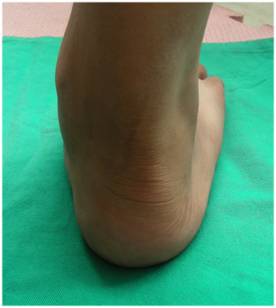

体格检查

详细而全面的体格检查,是评价扁平足畸形的严重程度;是否发生合并症;以及是否伴有关节退行性改变最基本的诊断方法。扁平足畸形通常表现为跟骨外翻,前足的内翻以及外展,有时会合并距下关节半脱位。临床检查通常以坐位、立位和行走时检查最为重要。